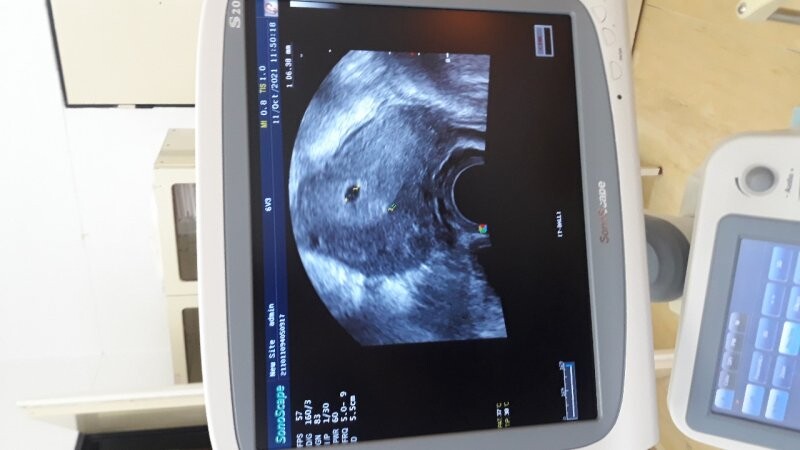

Dobrý den, chci se zeptat, co znamená dvojka na ultrazvuku viz foto. Děkuji

takto těžko hodnotit bez možnosti komplexního ultrazvukového vyšetření, nicméně to vypadá, že lékař jen omylem "odkliknul" další značku, která nic neznamená. Pro Váš klid se při další kontrole optejte, zda je vše v pořádku.